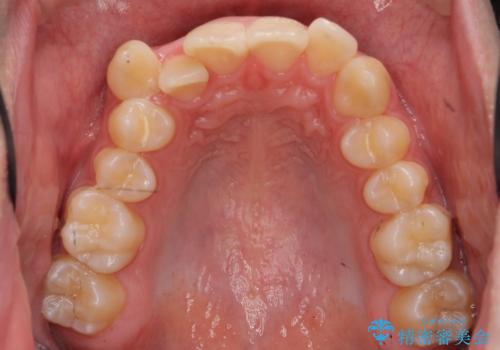

前歯のがたつき 下の八重歯

- 前歯のがたつきを主訴に来院。

上下左右の小臼歯を抜歯しています。

下のがたつきが大きいため、抜いたスペースをしっかり利用して並べるため矯正用インプラントを使用しています。